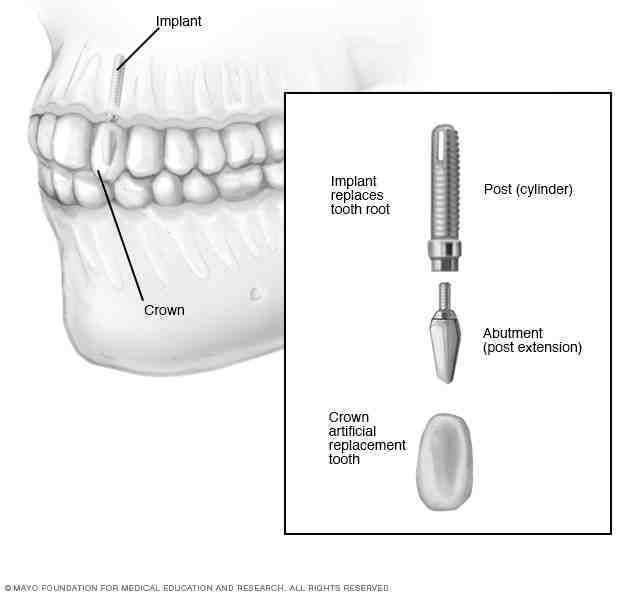

A periodontist is a dentist who specializes in the prevention, diagnosis, and treatment of periodontal disease, and the placement of dental implants. Periodontists are also experts in the treatment of oral inflammation.